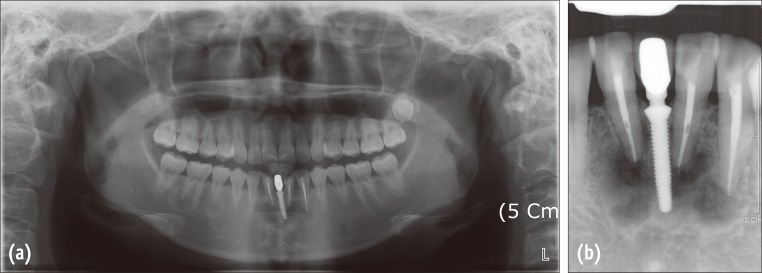

Figure 2

Radiographic examinations performed at the initial visit (in April, 2009) of the patient. (a) A panoramic radiograph showing multiple mixed radiopaque and radiolucent areas at the apices of the mandibular teeth; (b) A periapical radiograph of the lower anterior teeth. Two incisors and left canine were endodontically treated and an implant was included in the apical lesion.

Figure 2 Radiographic examinations performed at the initial visit (in April, 2009) of the patient. (a) A panoramic radiograph showing multiple mixed radiopaque and radiolucent areas at the apices of the mandibular teeth; (b) A periapical radiograph of the lower anterior teeth. Two incisors and left canine were endodontically treated and an implant was included in the apical lesion.